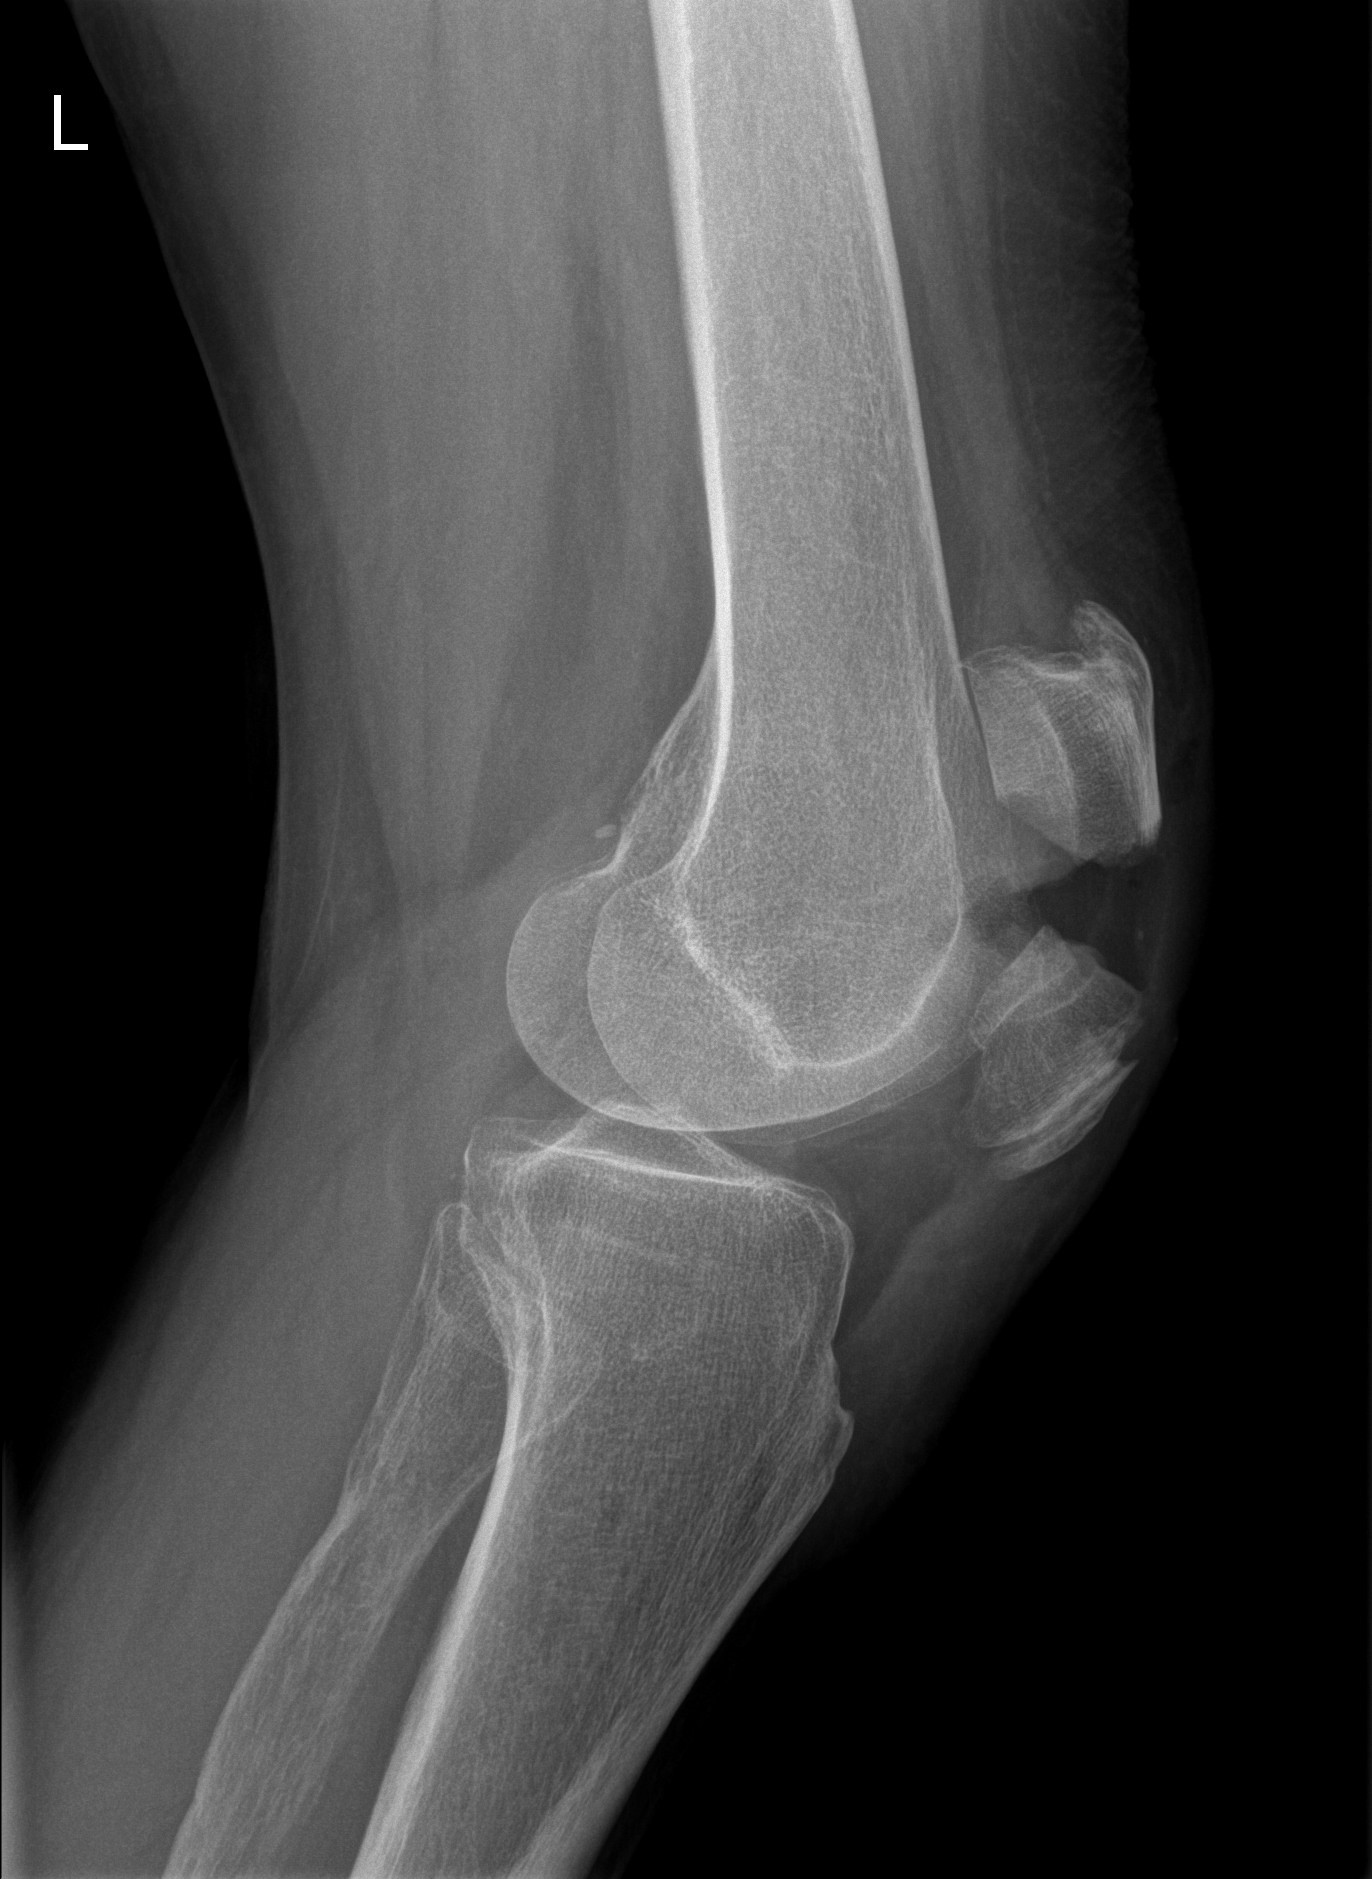

Kniefractuur

Breuk in of rond de knie na val of sportongeval? Kniefractuur diagnose en operatieve behandeling door kniespecialisten in Orthopedie Turnhout.